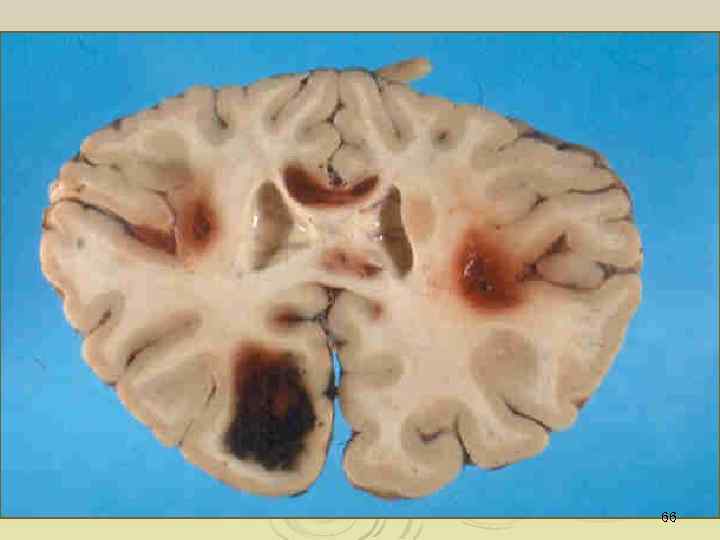

66